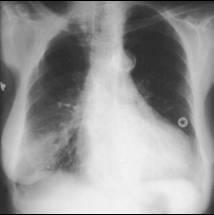

Lupus Pneumonitis